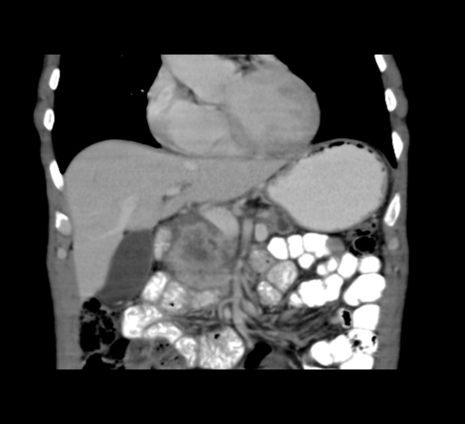

Case 2: Locally Advanced Tumor Presenting with Jaundice

A 55-year-old woman came in with two weeks of painless jaundice, darkened urine, and skin itching. Physical examination revealed jaundice and an enlarged, non-tender liver. Liver tests indicated cholestasis. CT scans revealed a 4.5 cm tumor in the pancreatic head surrounding more than 180° of the superior mesenteric arteries, making it inoperable. There was no distant spread, but the bile ducts were dilated. A biopsy confirmed pancreatic ductal adenocarcinoma. The patient began neoadjuvant chemotherapy with FOLFIRINOX. While the tumor reduced slightly in size, it remained unresectable due to vascular involvement. She received a stent to manage jaundice and lived for 16 months after diagnosis. This case illustrates the complex challenges involved in treating locally advanced pancreatic cancer.[165]

Figure 4 Tumor encasing SMA: Radiopaedia Case – Pancreatic adenocarcinoma vascular involvement